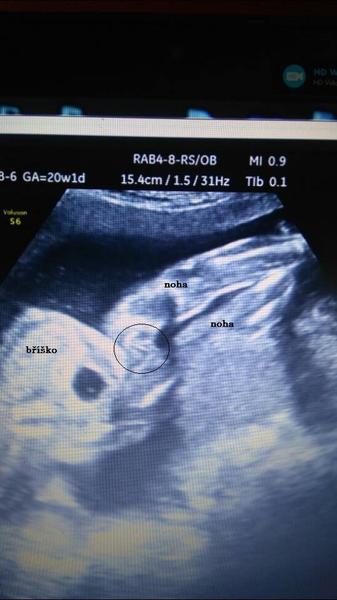

ahoj holky co si myslite je to kluk nebo holka ?dle dr cekame jistou holcicku jen me zarazi tady ta fotka me prijde jako pindik ,ale zase kdyz se zadivam poradne nevim nevim ...ale co jineho by to bylo?foto je z 20+1 vim ze bych mela verit dr fakt si byl jisty ale ja to tak zkoumala a pak narazila tady na toto 🙂